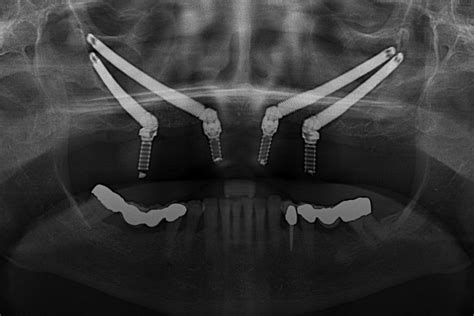

La principal diferencia entre los dos tipos de implantes dentales es la longitud y el espacio anatómico donde se colocan. Los implantes cigomáticos son más largos de los implantes convencionales, miden entre 35 y 55 mm de largo.

Para que la intervención sea exitosa, los implantes dentales deben anclarse en la mandíbula superior, cerca del hueso cigoma denso. Estos tornillos de hasta 52 milímetros llegan hasta el hueso de la mejilla para garantizar la resistencia y durabilidad.

El primer paso para colocar estos implantes dentales es acudir a la consulta de un experto en implantología, con experiencia y medios adecuados para llevar a cabo técnicas complejas como los implantes cigomáticos. Éste realizará las pruebas pertinentes: un estudio previo completo que incluye fotografías, radiografías y una tomografía computarizada (radiología tridimensional) para poder decidir si el paciente puede rehabilitarse con implantes convencionales, o si requiere implantes cigomáticos o por el contrario sería necesario realizar un injerto óseo o elevación del seno maxilar. Si se confirma que los implantes cigomáticos están indicados, el estudio permitirá saber cuántos necesitaría el paciente (pueden ser 2 ó 4) y qué posiciones serían las más adecuadas. El especialista se encargará de planificar de forma personalizada la cirugía.

La intervención quirúrgica para colocar los implantes cigomáticos comienza con la realización de una pequeña incisión en las encías del paciente para llegar a la mandíbula. Se coloca el implante de forma que roza o atraviesa los senos nasales y queda anclado al hueso cigomático. Actualmente los Dres. Peñarrocha colocan los implantes cigomáticos con cirugía guiada. Esto aumenta la precisión en la ubicación del éxtremo de dichos implantes, que se colocan en una zona no demasiado alejada del ojo. Este tipo de cirugía se realiza bajo anestesia general o sedación consciente intravenosa y anestesia local.